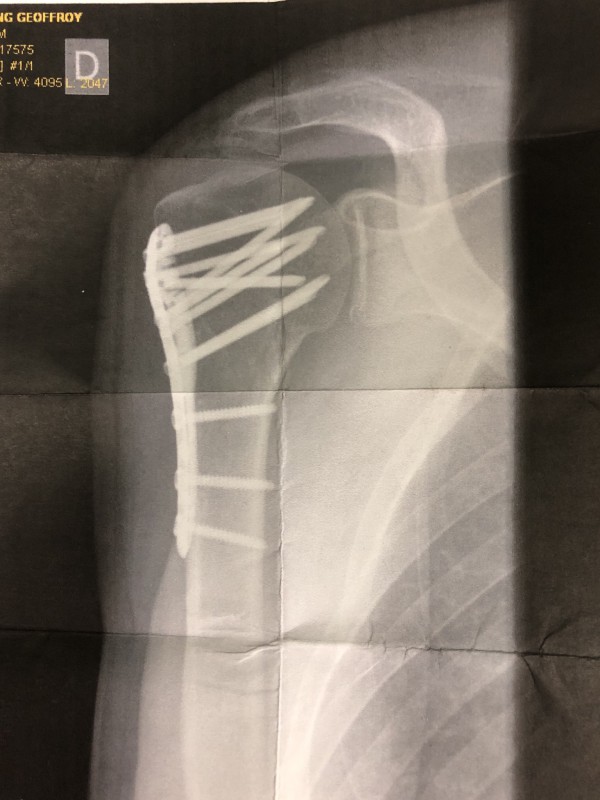

Oh la belle épaule...

Sympathique n'est-ce pas

Cassée déplacée

J'ai eu droit à la morphine

et voyage en helico autour du mont-blanc

Il y a 12 vis et une jolie plaque

Le tout en titane

C'est ça quand on n'a plus vingt ans

Ah oui j'entends encore le craaaaaaaaclaaaaac sur la belle plaque de verglas qui a fait office de piste d'atterrissage

Franchement j'ai morflé grave

Ca t'a pas besoin de le dire, la radio est parlante

geo ca me rappelle le temps ou je bossais dans une boite qui fabriquait (qui fabrique toujours d'ailleurs) des implants pour le rachissss, le costal et l'ablation du sternum

j'en ai vu passé des vidéos et autres photos en tout genre

on avait un système similaire de plaques et des vis (parmi tant d'autres) mais je dois avoué que le chir c'est fait plaisir au niveau des vis quand même...il avait peur que ça tienne pas ou il avait un nouveau tournevis comme joujou et il a pas pu s’arrêter